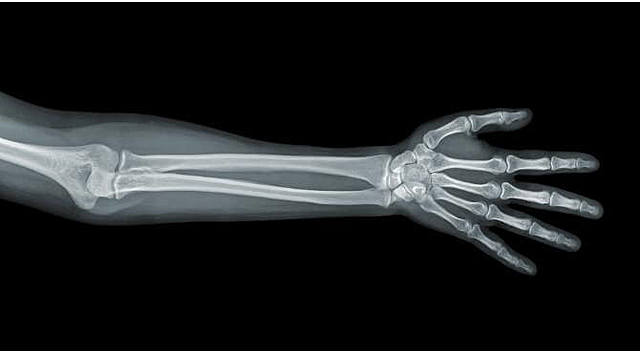

• Tomografia de Brazo Fracturado

Tomografia de Brazo Fracturado

En febrero de 1896 tomo una radiografía de un brazo fracturado y la mando al British Medical Journal extraordinario poder diagnostico